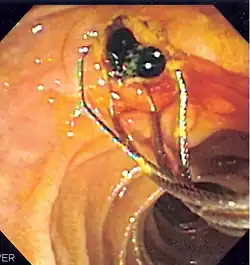

![]() Duodenoscopic image of two black pigment stones extracted from common bile duct after sphincterotomy | |

- Extraction of gallstones or other biliary debris[4]

When needed, the sphincters of the ampulla and bile ducts can be enlarged by a cut (sphincterotomy) with an electrified wire called a sphincterotome for access into either so that gallstones may be removed or other therapy performed.[10]

Other procedures associated with ERCP include the trawling of the common bile duct with a basket or balloon to remove gallstones and the insertion of a plastic stent to assist the drainage of bile.[11] Also, the pancreatic duct can be cannulated and stents be inserted.